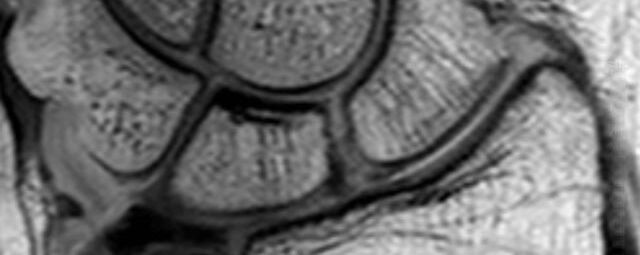

Gelenke

Hand

• Beurteilung von Knochen, Bändern und anderen Weichteilstrukturen der Gelenke nach Unfall.

• Arthrosediagnostik (Knorpelschaden)

• Impingement-Symptomatik

• Ursachenklärung bei wiederholter spontaner Gelenkluxation

• Ausbreitungsdiagnostik bei Gelenkentzündung, z.B. im Rahmen von rheumatischen Grunderkrankungen

Arthrographie

• MR-Arthrographie – nach örtlicher Betäubung und gründlicher Desinfektion der Haut wird unter Lagekontrolle mit Röntgen-Durchleuchtung eine kleine Nadel in den Gelenkraum positoniert und darüber ein MR-taugliches Kontrastmittel in den Gelenkraum gespritzt. Danach wird die Nadel entfernt. Anschließend erfolgt die MRT des Gelenkes. Diese Methode stellt kleine anatomische Strukturen des Gelenkraumes verbessert dar, z.B. zur Therapieplanung vor Arthroskopie bei Sportverletzungen der Schulter oder Gelenkinstabilität.